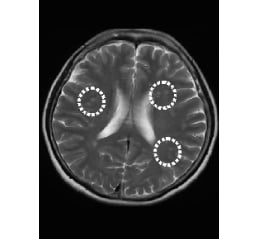

• MRI画像

脳腫瘍

微小脳梗塞

脳梗塞